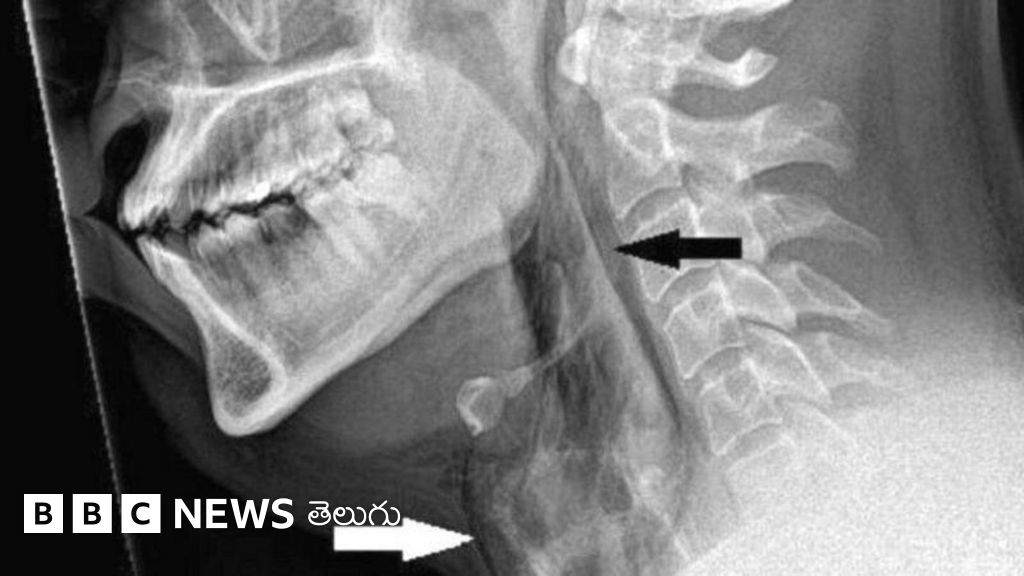

తుమ్మును ఆపేందుకు ప్రయత్నించిన వ్యక్తికి గొంతులో తీవ్ర గాయమైన ఘటనతో స్కాట్లాండ్ వైద్య బృందం ఒక హెచ్చరిక జారీ చేసింది.

స్కాట్లండ్లోని డుండీలోని నైన్వెల్స్ ఆస్పత్రికి 30 ఏళ్లున్న ఒక రోగిని తీసుకొచ్చారు. తుమ్ము వస్తోందని నోరు, ముక్కు మూసుకోవడంతో గొంతులో తీవ్రమైన నొప్పి ఏర్పడిన కారణంగా ఆయన్ను ఆస్పత్రికి తెచ్చారు.

అలా నోరు, ముక్కు మూసుకోవడంతో అతని శ్వాసనాళం 2 మిల్లీమీటర్ల మేర చిరిగిపోయిందని స్కానింగ్లో తేలింది.

తుమ్ములు వచ్చేప్పుడు నోరు, ముక్కు మూసుకుంటే శ్వాసనాళం ఎగువ భాగంపై దాదాపు 20 రెట్లు ఎక్కువగా ఒత్తిడి పడుతుందని డుండీ యూనివర్సిటీ వైద్యులు చెప్పారు.

వైద్యులు రోగిని పరీక్షిస్తూ అతని గొంతును తాకినప్పుడు లోపల పగుళ్లు వచ్చిన శబ్దం వినిపించింది. అలాగే, గొంతు కదలికలపై అతని నియంత్రణ లేదని గుర్తించారు.